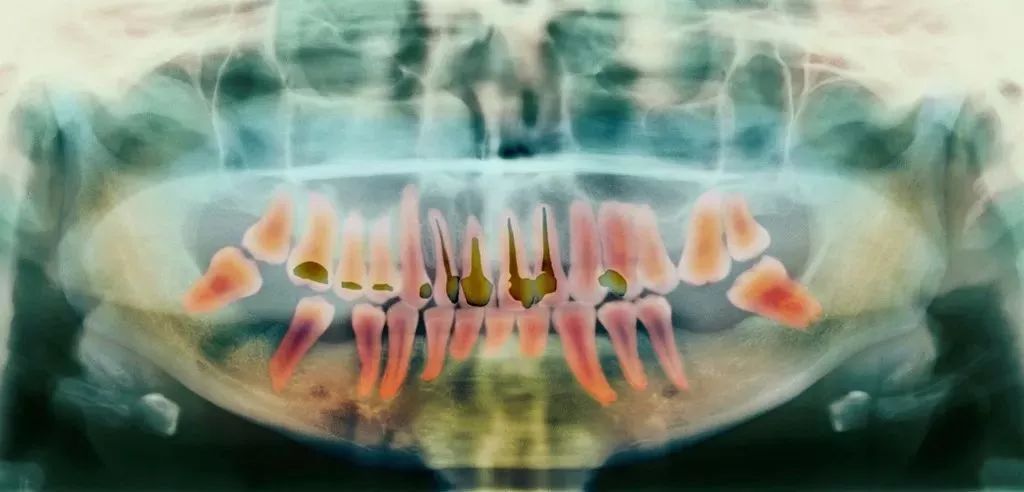

前牙根管需要治疗的牙根数量少,价格也就相对便宜;反之,后牙相较于前牙的价格会贵,双尖牙的根管治疗是最难的,因此,根管治疗的价格也是最贵的。

另外,除了根管治疗本身的费用外,还需要加上手术后保护牙齿的牙冠费用,而牙冠的价格,主要与材料有关。